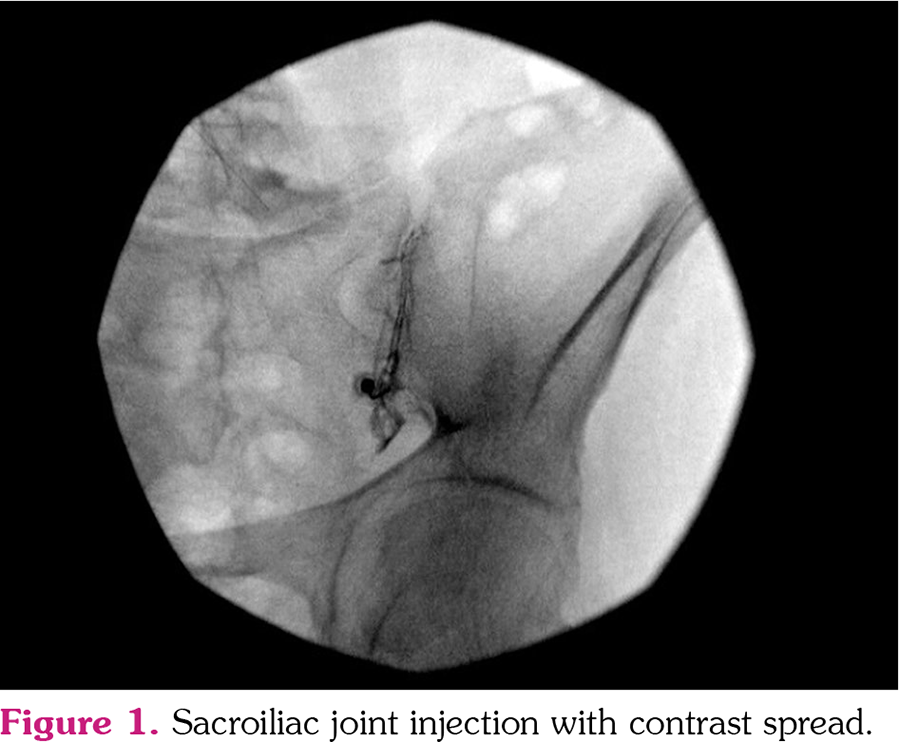

Duration of symptoms/month was 5.5±3.4 in the injection group (mean age 33.4±5.9 years; range, 23 to 44 years) and 6.7±3.8 in the non-injection group (mean age, 29.9±6.2 years; range, 18 to 43 years). Both groups were similar with regard to demographic data (age, sex, socioeconomic status, and work status), AS/nr-axSpA patient ratio, and symptom duration (p>0.05). The participant flow diagram is presented in Figure 2.